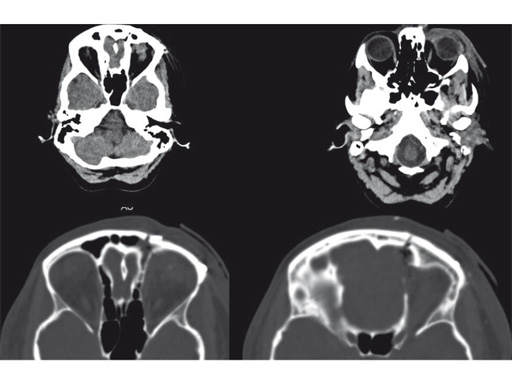

Resection of orbital lymphangioma in a 29-year-old woman.

Case provided by Christian Matula, Wien, Austria

Fig 3 Postoperative images.